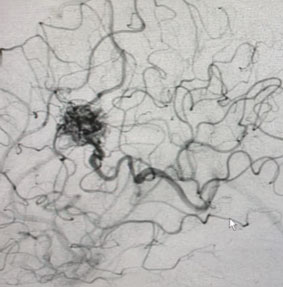

MRI was consistent with a left deep frontal AVM (Figure 2).

Fig. 2